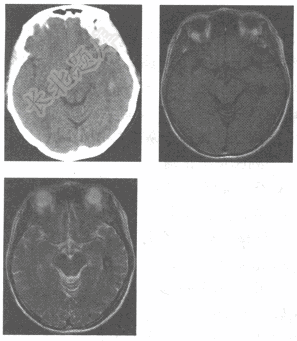

- 单项选择题女性患者,49岁,发作性头晕4小时余。查体:神清语利,颅神经(-),高血压病史5年。CT及MRI检查如图,最可能的诊断为

A、脑囊虫病

B、海绵状血管瘤

C、脑出血

D、脑胶质瘤

E、脑梗死